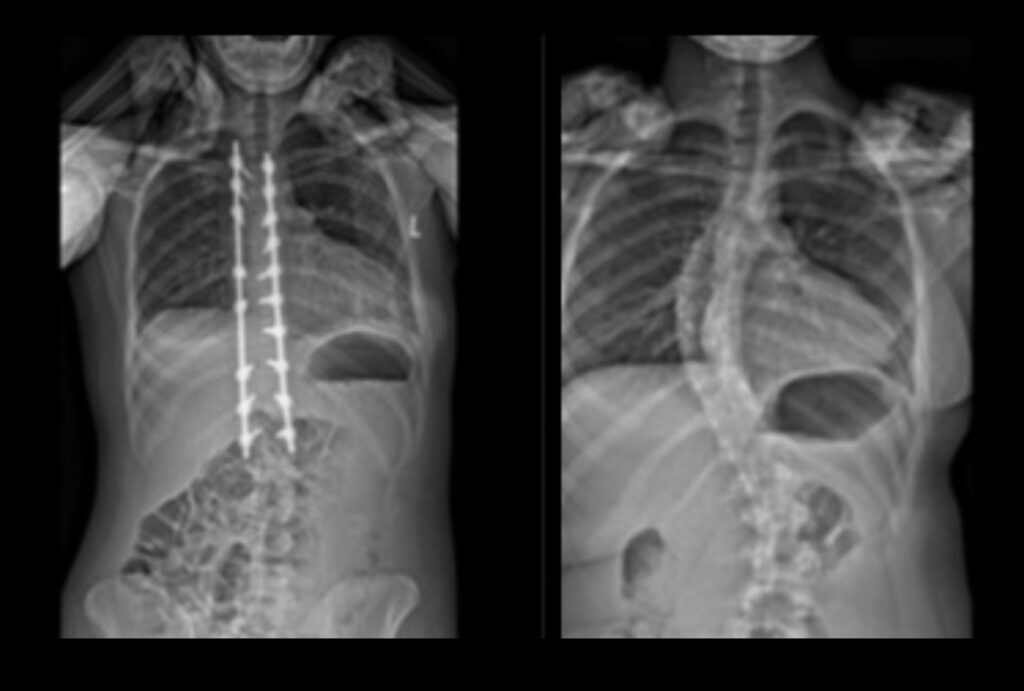

Every year my school district requires a physical from a pediatrician. Here, they do all the basic measurements and tests necessary to ensure I am healthy. At my physical for the start of middle school (sixth grade), I bent to touch my toes and my doctor measured my back. After this instance, my diagnosis of scoliosis was a blur. I remember visiting an orthopedist, taking x-rays, and getting measured for a brace.

At my next appointment, we came to the decision that my curve had simply progressed too far and a spinal fusion was necessary. On January 6, 2021, I had my spinal fusion. I used all the ambition and mental toughness from wearing my brace to strengthen my body after surgery by committing to physical therapy and strength training. I worked as hard as I could to get back into playing volleyball and to discipline myself to work hard in school. Over the last two years I have conducted research regarding scoliosis and self-esteem. I was able to talk to teenagers across the United States about their feelings and experiences, finally feeling like I was never truly alone throughout my scoliosis journey. I am now a senior, captain of my high school’s volleyball team, and applying to colleges with the drive to become a physical therapist.